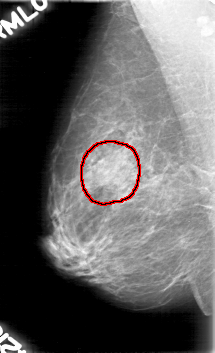

FILE: D_4023_1.RIGHT_CC.OVERLAY

TOTAL_ABNORMALITIES 1

ABNORMALITY 1

LESION_TYPE MASS SHAPE OVAL MARGINS OBSCURED

ASSESSMENT 0

SUBTLETY 2

PATHOLOGY BENIGN

TOTAL_OUTLINES 1

BOUNDARY